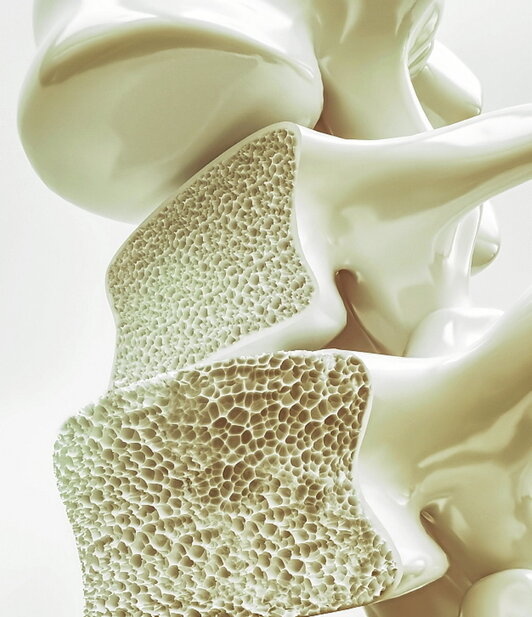

Gure gorputzaren hezurdura, alde batetik, kolagenoz osatuta dago, malgutasuna eta egitura ematen diona eta, bestetik, kaltzioak eta fosfatoak gogortasuna ematen diona, beste mineral batzuekin batera. Egitura hau egokia izateko eta inguratzen dituen organoak babesteko, ezinbestekoa da indartsua eta aldi berean malgutasun puntu bat izatea. Gainera, hezurrak berritze prozesu konstante batean daude, egitura osasuntsu mantentzeko helburuarekin zelulen birsortze jarraitu bat eginez. Hala ere, urteekin prozesu hau moteldu egiten da, berritze prozesuaren gaitasuna gutxituz, eta aldi berean gaixotasunak agertu daitezke.

Osteopeniaren kasuan, hezurren dentsitatea gutxitzen da, balore normaletatik jaitsiz. Faktore hau agertzearen arriskua bereziki emakumeengan menopausia prozesuan, jarduera fisiko gutxi egiten duten pertsonengan edota Bitamina D eta kaltzio gutxi duten dietek dituzten pertsonengan areagotzen da.

Osteoporosiaren kasuan, aurreko patologiaren ondorengo urratsa da, non hezurraren ahulezia handiagoa den eta hauek hausteko arriskua handia den. Kasu honetan, dentsitatea oso baxua da, eta emakume zaharrengan areagotzen da, menopausia igaro ondoren.

Osteomalazia, berriz, hezurren gaixotasun bat da, non mineralizazioa eskasa den eta, horren ondorioz, hezurrak bigundu egiten diren. Normalean Bitamina D faltagatik izaten da, honek kaltzioaren mineralizazioaren prozesuan laguntzen baitu, hezurrari gogortasuna emanez.